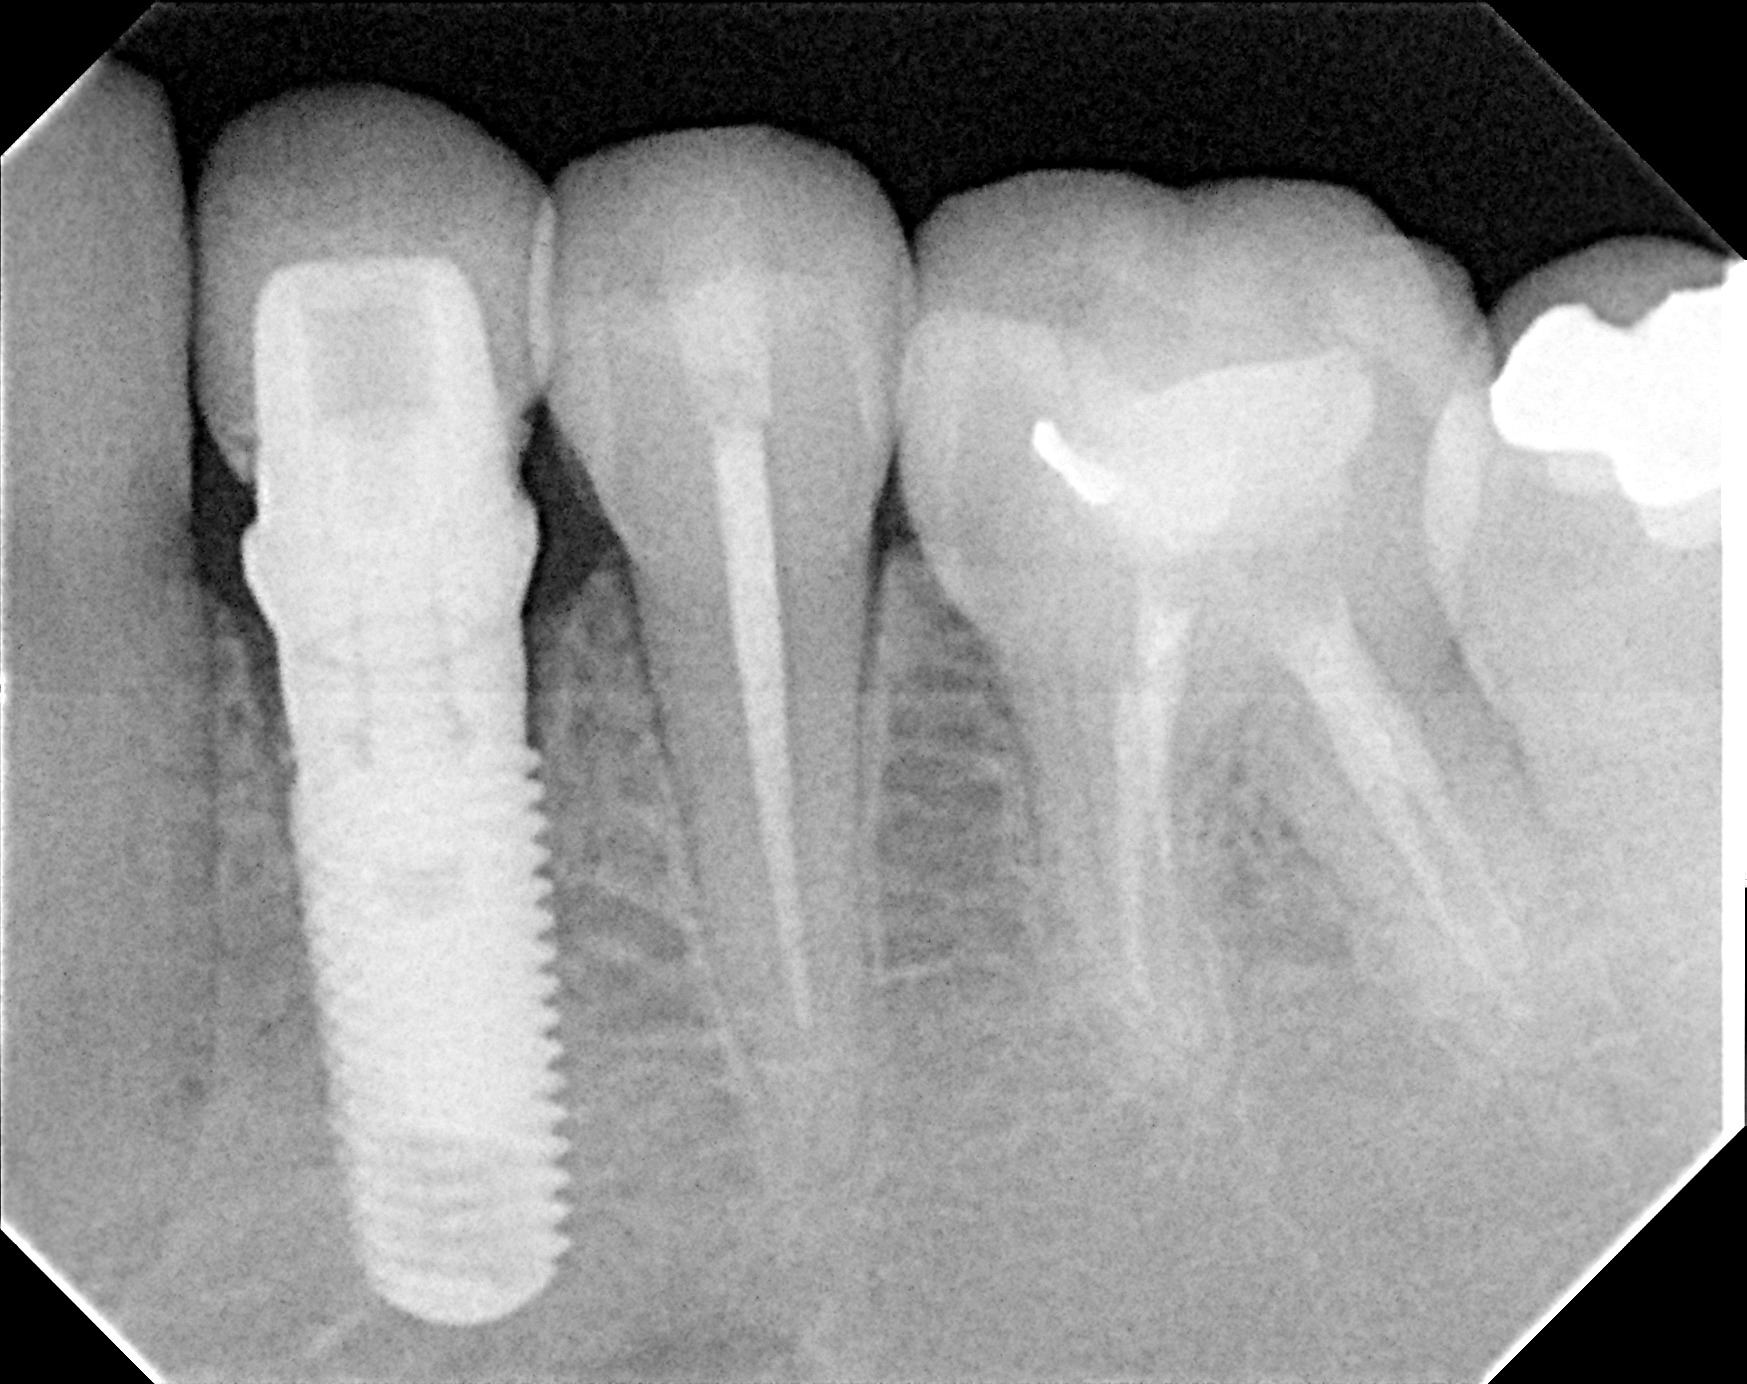

Methods: It was a case report of a 25 year old female patient who presented to dental clinic AKUH with the complaints of mobility in a tooth in lower left jaw. On clinical and radiographic examination her first premolar was periodontaly compromised and had a hopeless prognosis.An atraumatic tooth extraction was done under local anaesthesia and a Zimmer implant was immediately placed, primary stability achieved to 30Ncm. Temporary crown was placed on the implant on the same day using patient’s own pre extraction record. Her bite was adjusted to keep tooth slightly off occlusion.After a 2 weeks interval, excellent tissue healing was achieved and permanent crown was placed using cemented retention.